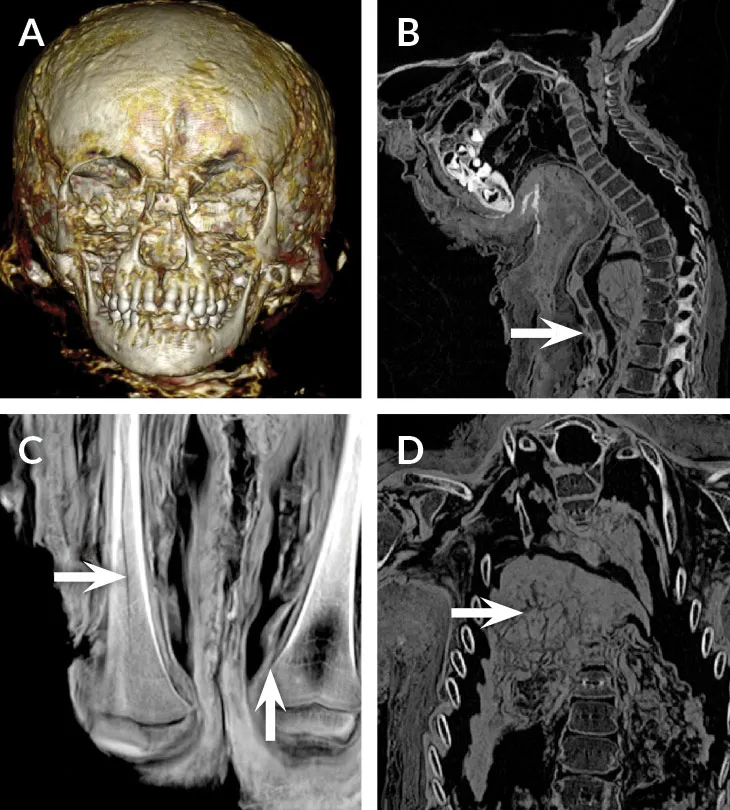

MUMMY MYSTERY Little was known about this mummified Egyptian child (top) when German physicist Walter Koenig used X-rays to look beneath its wrappings in 1896. Modern CT scans provided a more informative peek, revealing, among other findings, a completely preserved skeleton (bottom).

S. Zesch et al/Euro. J. Radiol. Open 2016